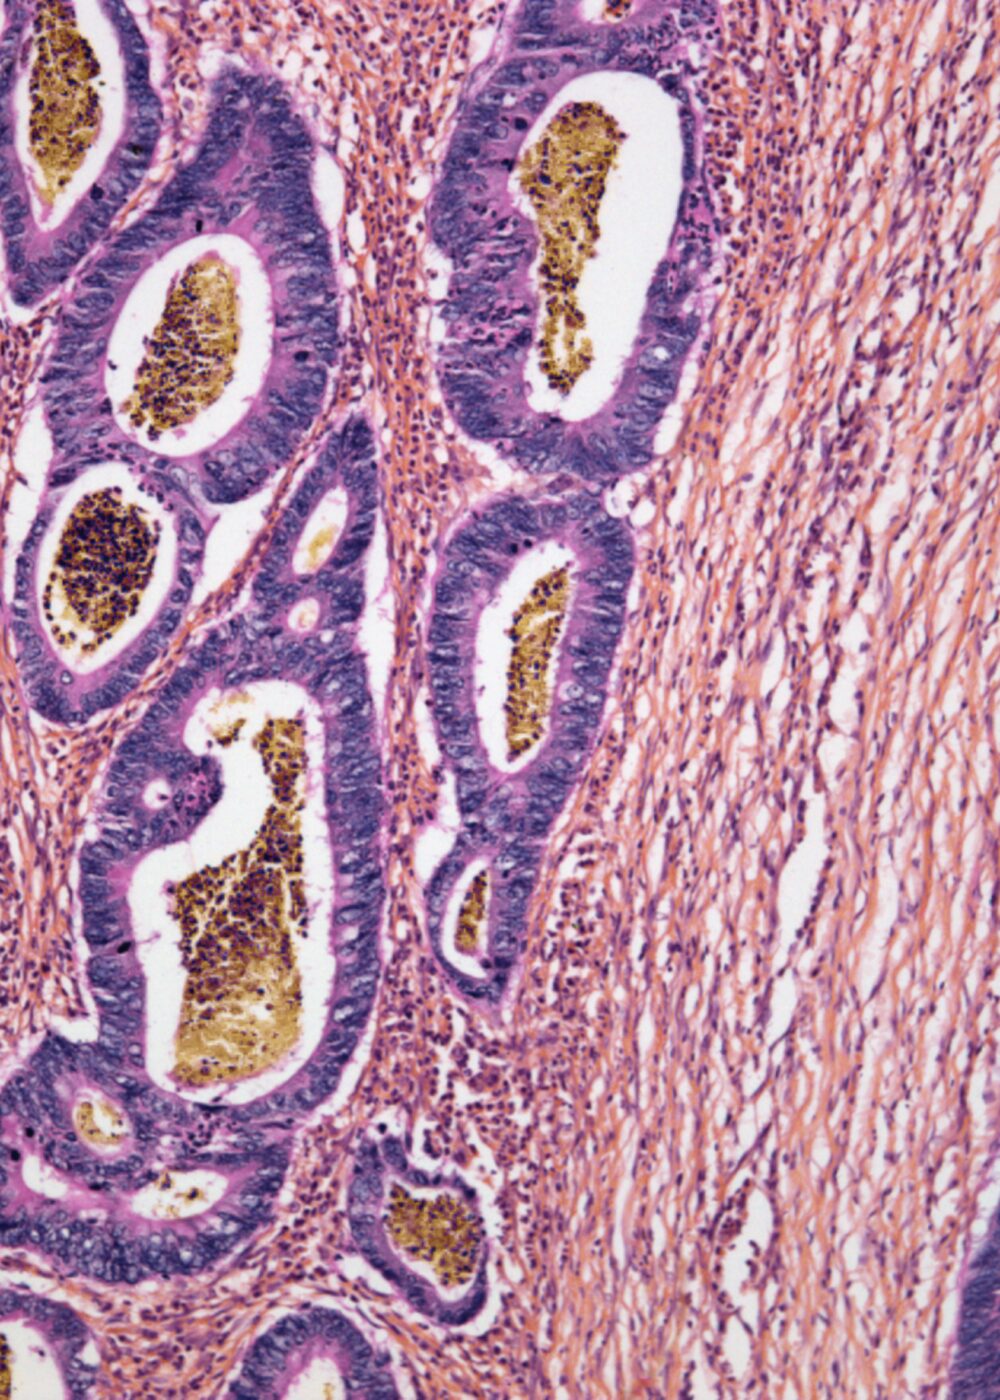

Light micrograph of colorectal cancer. Source: Getty.